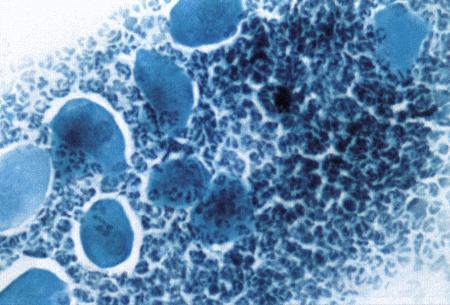

Вагинальная эндоскопия

Прекращение секреции эстрадиола фолликулами и переход их к секреции прогестерона приводят к снижению как отечности, так и васкуляризации слизистых оболочек, что сопровождается выраженным изменением характера вагинальных выделений, выявляемым с помощью вагинальной эндоскопии. На стадии проэструса слизистая оболочка становится более выпуклой и отечной, затем наблюдается ее уменьшение; по мере приближения овуляторного пика слизистая сжимается и бледнеет, в некоторых случаях становясь практически белой (фиг. 1.1). Перечисленные изменения свидетельствуют о приближении стадии, характеризующейся постепенным повышением концентрации прогестерона перед овуляцией и последующим наступлением фертильного периода. Эти изменения легко узнать, имея даже небольшую практику (фиг. 1.3), кроме того, они настолько воспроизводимы, что по набору признаков их можно оценивать полуколичественно. Вагинальная эндоскопия весьма полезна в определении оптимальных сроков вязки. По окончании фертильного периода, т. е. в начале метэструса — слизистая оболочка влагалища бледнеет и истончается, складки становятся закругленными — и что, вероятно, является наиболее характерным признаком, — слизистая в переднем отделе влагалища выглядит раздраженной и при прикосновении быстро сжимается, образуя розетку.

Фиг. 1.3.

Эндоскопическое исследование слизистой влагалища. Динамика изменений на протяжении цикла: (а) проэтрус — розовая окраска и отечность; (b) начало эструса — слизистая бледнеет, отек начинает уменьшаться (обычно перед пиком ЛГ); (c) середина эструса — слизистая бледная, уменьшение отека (сморщивание) явно выражено, что соответствует середине фертильного периода; (d) начало метэструса — видны закругленные складки, при прикосновении слизистая смыкается, образуя розетку (е) (см. Приложение)